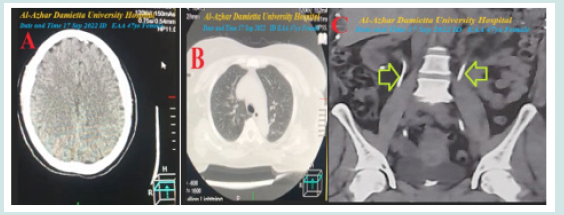

The random blood sugar was 119 mg /dl. CBC showed; Hb was 8.7 g/dl, RBCs; 3.39*103/mm3, WBCs; 9.5*103/mm3 (Neutrophils; 80.4 %, Lymphocytes: 9.6%, and Mix 10.0%), Platelets; 268*103/mm3. Serum creatinine (4.2mg/dl), serum ionized calcium (6.5mg/dl), serum magnesium (1.7mg/dl), serum potassium (5.3mmol/L), serum phosphate (7.3mg/dl), and plasma sodium (148 mmol/L). Plasma TSH (3.43mU/L). HA1C (5.9%). Two calcium gluconate ampoules (10 ml 10% over IV over 20 minutes) were given as an emergency dose and repeated every 12 hours. The second ECG tracing was taken within 45 minutes of the above ECG tracing showing NSR of VR 94 bpm with the disappearance of the above Wavy triple sign (Yasser’s sign). There is a single premature ventricular complex (PVC) in V2 (Figure 1B). The brain CT scan was done within 1 day before ICU admission showing no abnormalities (Figure 2A). The chest CT was done 1 day before ICU admission also showing no abnormalities (Figure 2B). The abdominal CT scan was done 1 day before ICU admission showing evidence of bilateral ureteric stents (Figure 2C). Within 48 days of the above management, the patient finally showed nearly dramatic clinical and electrocardiographic improvement. Wavy triple sign (Yasser’s sign) with hypocalcemic convulsive diagnosis in generalized convulsions with diabetes, chronic renal failure, and stone was the most probable diagnosis. The patient was discharged after clinical stabilizations and continued twice daily Oral calcium and vitamin D preparation were prescribed for life-long. Further recommended cardiac urological, neurological, and endocrinal follow-up was advised.

Figure 2: A-section of the brain CT scan was done 1 day before ICU admission showing no abnormalities. B-section of chest CT scan was done 1 day before ICU admission showing no abnormalities. C-section of abdominal CT scan was done 1 day before ICU admission showing evidence of bilateral ureteric stents (lime arrows).

e) Abdominal CT showed bilateral ureteric stents supporting the diagnosis of stented ureteric stones (Figure 2C).